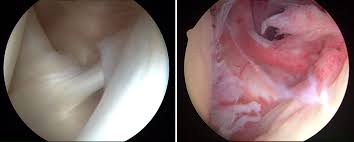

최근에는 관절경으로 두꺼워진 관절낭을 제거하는 수술이 있습니다. 견관절 구축이 매우 심한경우 시행해 볼 수 있으며 예후가 좋습니다. (관절낭의 해리는 Posterosuperior -> Posterior -> Anterosuperior -> anterior -> inferior 순서로 시행합니다. 마지막에 Synovectomy 도 같이 시행합니다. )